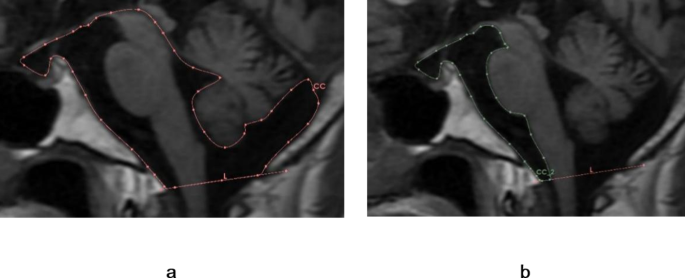

The brainstem pericistern refers to the CSF space formed around the brainstem, and is primarily an amalgamation of the interpeduncular, prepontine, pontocerebellar, pre-medullary, cerebellomedullary, occipital, and quadrigeminal cisterns (Fig. 4a). In longitudinal sections, this region mainly includes the interpeduncular, prepontine, and medullary cisterns (collectively called the prepontine cistern) (Fig. 4b), the mesencephalic aqueduct, fourth ventricle, and cerebellomedullary cistern. The lower edge is bounded by the foramen magnum.

Illustration of cisternal spaces surrounding the brainstem. (a) The total cisternal space is composed primarily of the interpeduncular, prepontine, medullary, and cerebellomedullary cisterns. The cerebral aqueduct and fourth ventricle are also shown. (b) Prepontine cistern in sagittal cross-section resembling a hammer.

Measurement of prepontine cistern area

In individuals with iNPH, the dilated prepontine cistern space resembled a “hammer” in sagittal cross-section (Fig. 6a, b and c). To define this “hammer” shape qualitatively, we established the following criteria: (i) prepontine cistern area > 5 cm2, (ii) gap between the sella floor and the optic nerve > 2.5 mm (Fig. 6d, line L), (iii) interpeduncular cistern height > 5 mm (Fig. 6d, line L1), and (iv) the distance between the most prominent part of the anterior ventral brainstem and clivus > 5 mm (Fig. 6d, line L2). According to these criteria, the “hammer sign” was present in 94.0% of NPH patients but only 20.0% of healthy individuals (Table 13).

Illustration of the hammer sign as a marker for iNPH. (a) and (b) The ‘hammer’ shape of the prepontine cistern in patients with iNPH as seen on T1WI images. (c) Expansion of the prepontine cistern presents a “hammer-like” shape. (d) Line L: Gap between the sella floor and the optic nerve, Line L1: Height of the interpeduncular cistern, Line L2: Distance between the most prominent anterior ventral aspect of the brainstem and the clivus.